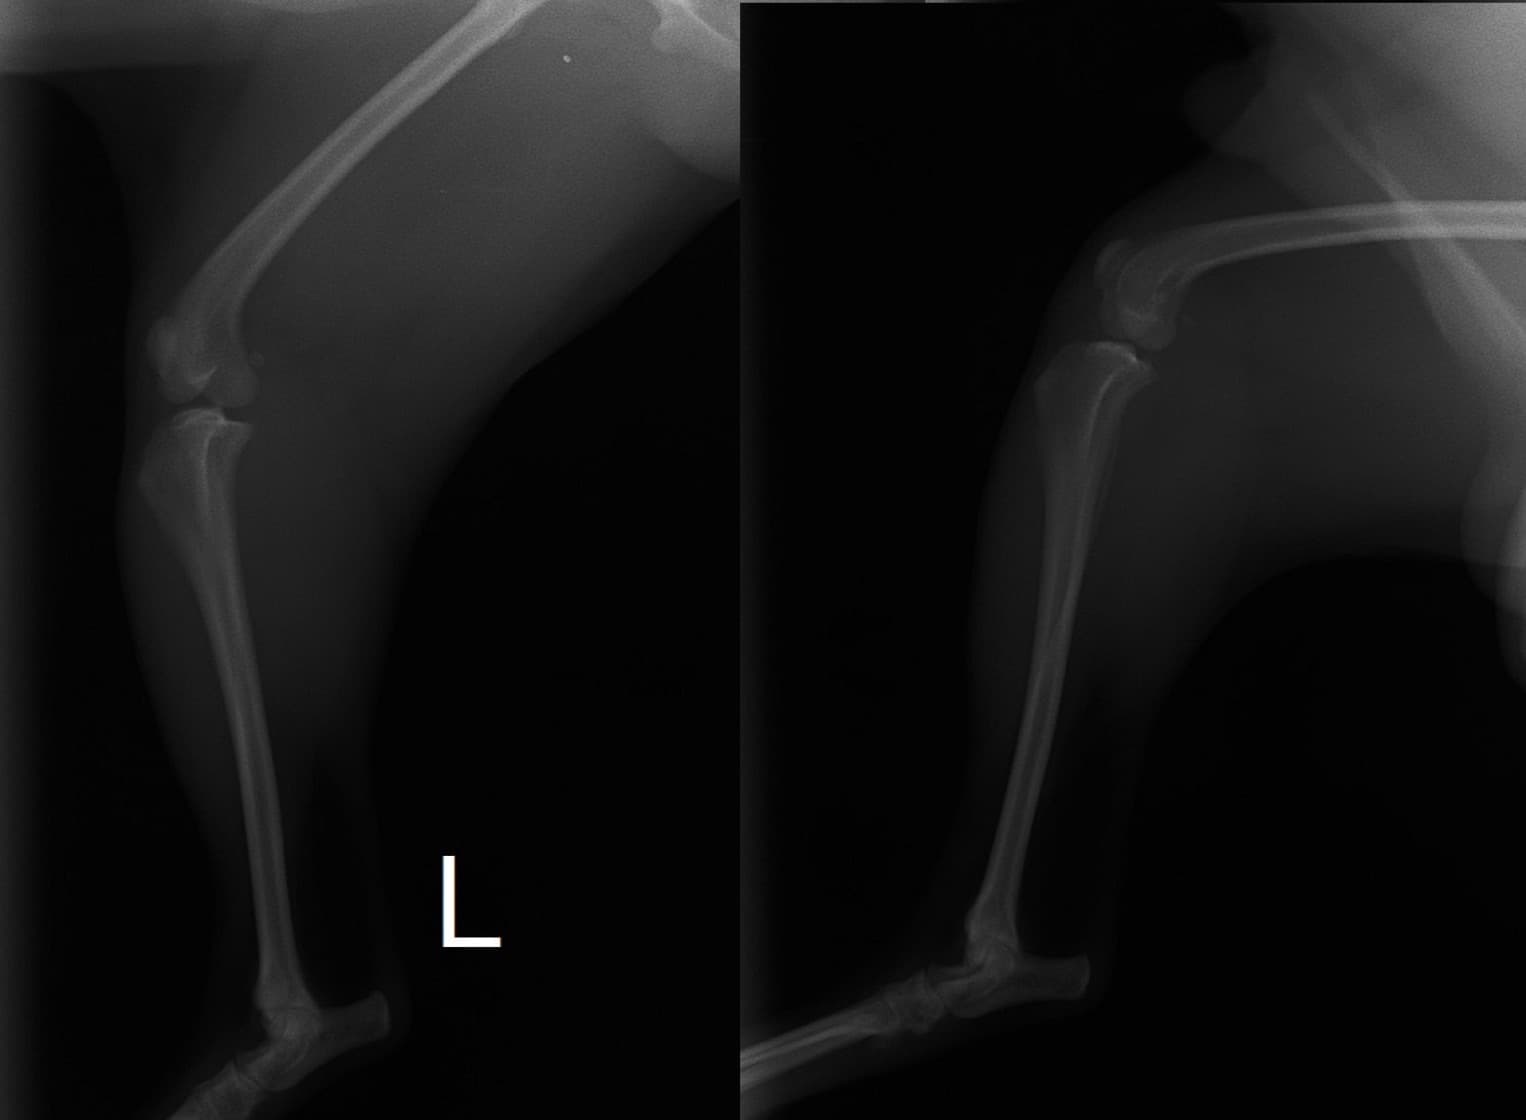

■ 症例20 ポメラニアン 8ヶ月 1.8kg

左右膝蓋骨脱臼 グレードⅢ

2ヶ月前から間欠的跛行が認められ、両膝の膝蓋骨脱臼整復術を行った。

手技は縫工筋及び内側広筋の解放、脛骨粗面の外側転位、滑車ブロック形造溝術、内外側関節包の縫縮を選択し実施した。

右側の膝蓋骨脱臼は上記手技で整復されたものの、左側はそれのみでは膝蓋骨が浮く様子が認められた。その為、PDS縫合糸にて膝蓋靱帯を1糸のみ縫合し、靱帯の縫縮を行った。

膝蓋骨脱臼は膝関節における膝蓋骨の内外側の脱臼と定義されるが、時として単純な内外の脱臼ではなく、膝蓋骨が大きく前方に浮き上がるように脱臼する場合がある。特にトイプードルやポメラニアンといった犬種に多く認められる。

内側脱臼に加えて前方への浮き上がりを矯正する為に、従来より脛骨粗面転移により膝蓋靭帯を外方と下方に引っ張り、固定する方法を選択する。膝蓋骨の前方への浮き上がりが軽度の場合は、従来法ではなく関節包の縫縮で対応していた。しかし、一部の症例で膝蓋骨の動きが悪くなり伸展機構が円滑に機能せずロボット様歩行になるケースがあった。

その為、膝蓋靭帯自体を縫縮する方法を採用した。この方法により、膝関節の伸展機構を妨げず膝蓋骨の軽度の浮きを矯正することが可能となった。

本症例の経過は良好である